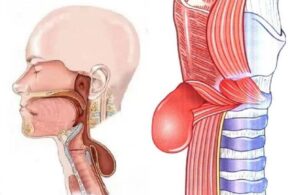

В Алматинской многопрофильной клинической больнице проведена уникальная операция пациенту 1954 года рождения, который более 30 лет страдал нарушением глотания. Диагноз – дивертикул Ценкера, редкая патология, встречающаяся примерно у 3,5% пациентов с заболеваниями пищевода.

Мужчина на протяжении десятилетий испытывал серьёзные трудности при приёме пищи. Последние годы состояние резко ухудшилось: пища застревала, приходилось самостоятельно надавливать на шею, чтобы она частично проходила в желудок. Остальное выходило наружу с рвотой. За последние 2–3 года пациент потерял около 20 кг и оказался на грани истощения.

Операцию провёл хирург Алматинской многопрофильной клинической больницы Айазбаев Нурбол Бейсенович. В ходе вмешательства удалось освободить пищевод в области шейного отдела и удалить расширенный участок.

«Дивертикул Ценкера — серьёзная и коварная патология. Пациенты годами живут с дисфагией, не зная точного диагноза. В данном случае операция была крайне необходима, поскольку речь шла не только о качестве, но и о сохранении жизни. Мы рады, что пациент успешно перенёс лечение», — отметил врач.